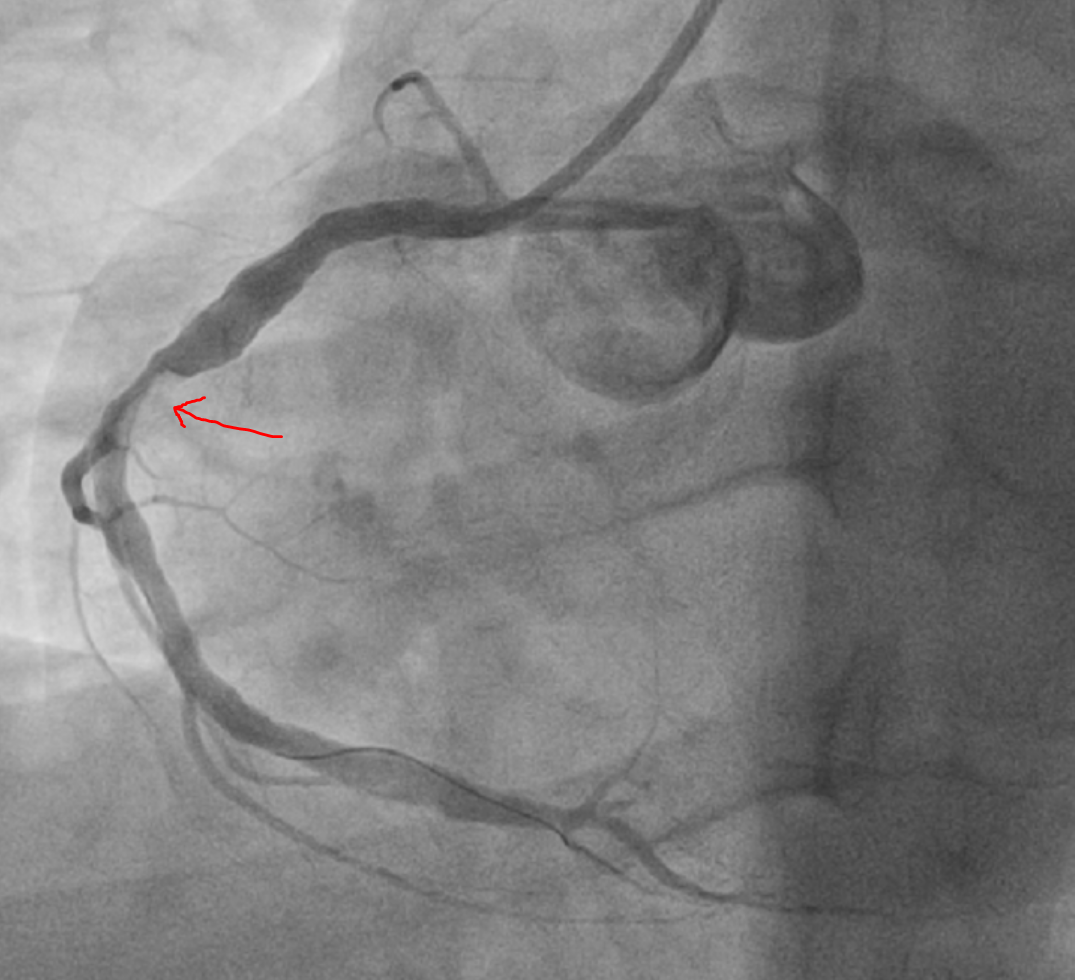

После два стента с таким результатом:

Upd: кому интересна левая коронарная артерия: